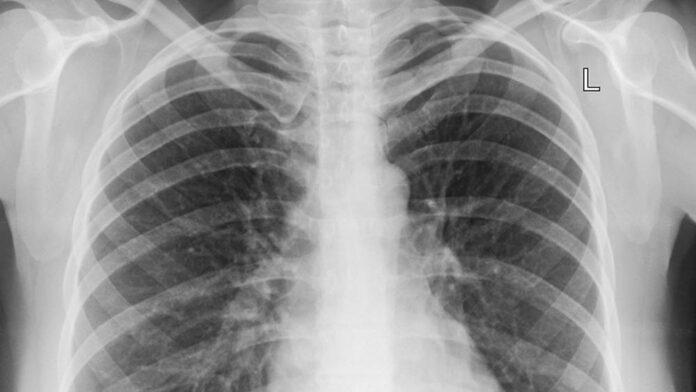

O diagnóstico é confirmado por exames como radiografia do tórax e análises de sangue, que ajudam a identificar o agente causador e direcionar o tratamento.